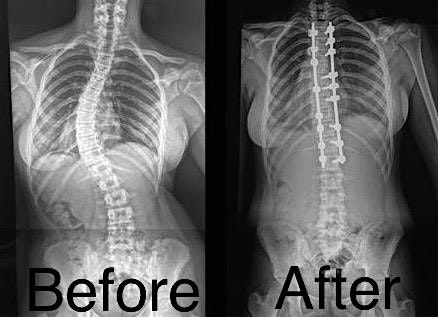

Join us for an evening at Topgolf featuring golf, a buffet dinner, and non-alcoholic beverages. Proceeds will support our upcoming mission to Santiago, Dominican Republic, where we will provide life-changing scoliosis surgery for 7–8 children.